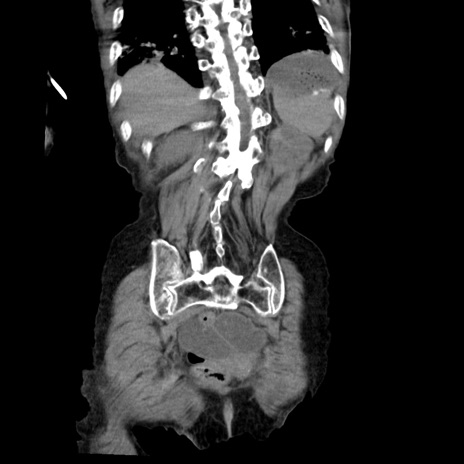

症例27(冠状断像)

【症例】80歳代女性

【主訴】嘔吐、腹痛

【現病歴】数時間前より嘔吐あり。心窩部痛出現し、徐々に右下腹痛あり。その後も数回嘔吐あり救急搬送となる。

【既往歴】左大腿骨頚部骨折手術

【身体所見】腹部は膨隆しているが軟らかく圧痛なし。腸雑音はやや亢進。

【データ】WBC 12000、CRP 19.05